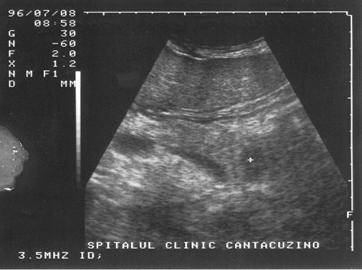

Imaginea transsonica

Structurile lichidiene (sangele, bila, secretiile digestive, continutul chistelor, ascita, colectia pleurala) sunt strabatute de catre ultrasunete in totalitate, fara a exista nici un fel de reflexii pe traseul acestora. Imaginea ecografica, fiind expresia unei "lipse de ecouri", va avea aspectul opus structurilor ecogene, respectiv culoarea neagra. O structura lichidiana este definita in ecografie prin termenul de transsonic.

Exemple:

structuri transsonice normale: colecist, vezica urinara, lumen vascular;

structuri transsonice patologice: chistul, continutul necrozat al unui abces sau al unei tumori maligne.

Figura 1. Vezica urinara

Figura 2. Chist renal stang situat in treimea medie

Figura 3. Chist ovar drept

Figura 4. Chist hepatic